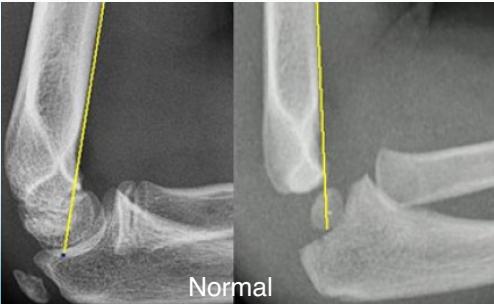

Fat Pad Sign:

- Posterior fat pad always appears in bleeding/hemoarthrosis - always abnormal

- Anterior fat pad may appear in bleeding

Important: If there’s no fracture line but there’s fat pad, treat it as minimally displaced with back slab for 2-3 days and repeat X-ray

Lateral elbow X-ray image

- Fat pad sign:

- Indicates a fracture (posterior is always abnormal)